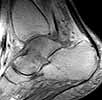

58 y/o female, had ankle sprain 3 months ago. First avulsion fracture on the tip of fibula was diagnosed and cast was applied for four weeks. After cast removal pain and swelling did not subside.

Now has mild swelling at ankle. Walks with cruches, weight bearing is not possible due to pain.

I think there was a nondisplaced talar neck fracture with complicated by AVN.

Current X-ray shows sclerosis of talar body, destruction at talar dome. MRI shows diffuse swelling in talus (interesting where comes the swelling if there is avascularity?). CT does not surely confirm fracture but shows diffuse osteoporosis in tarsal bones.